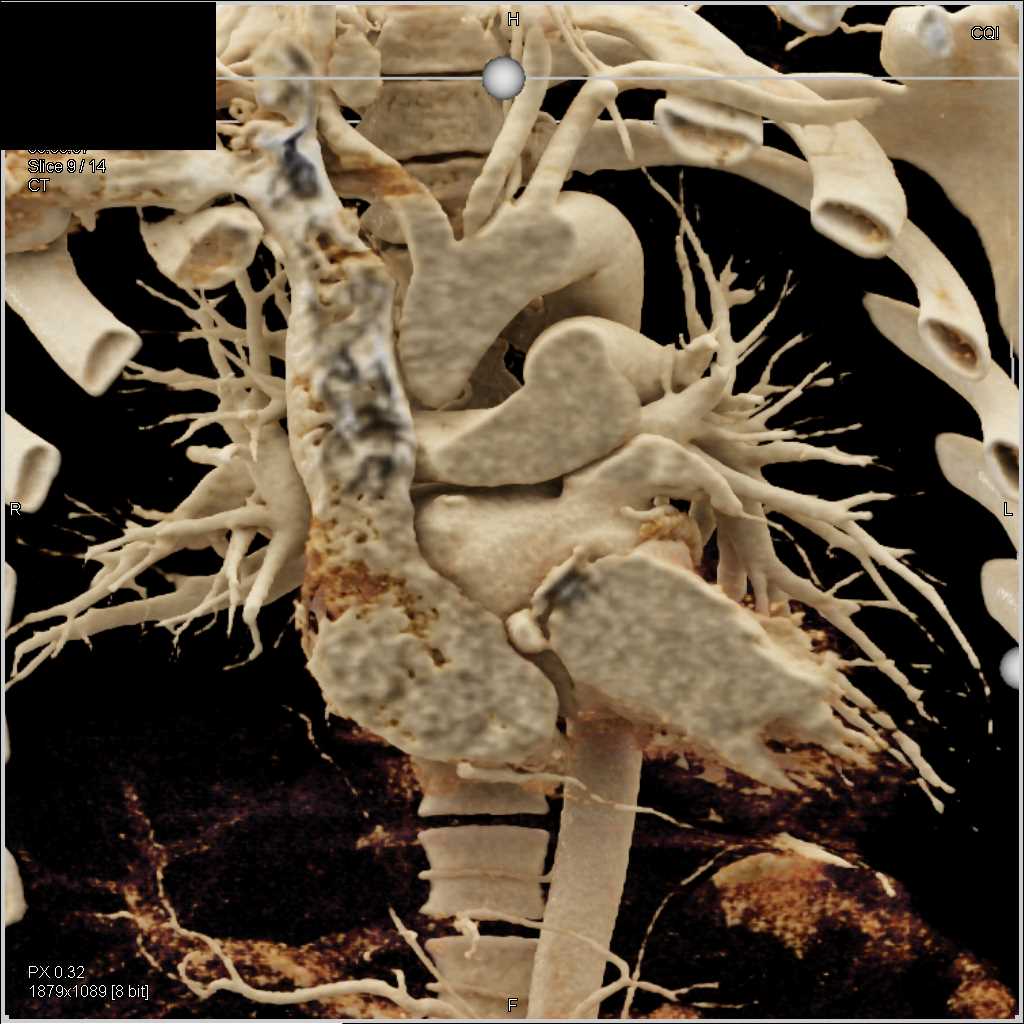

Aortic Valve Repair